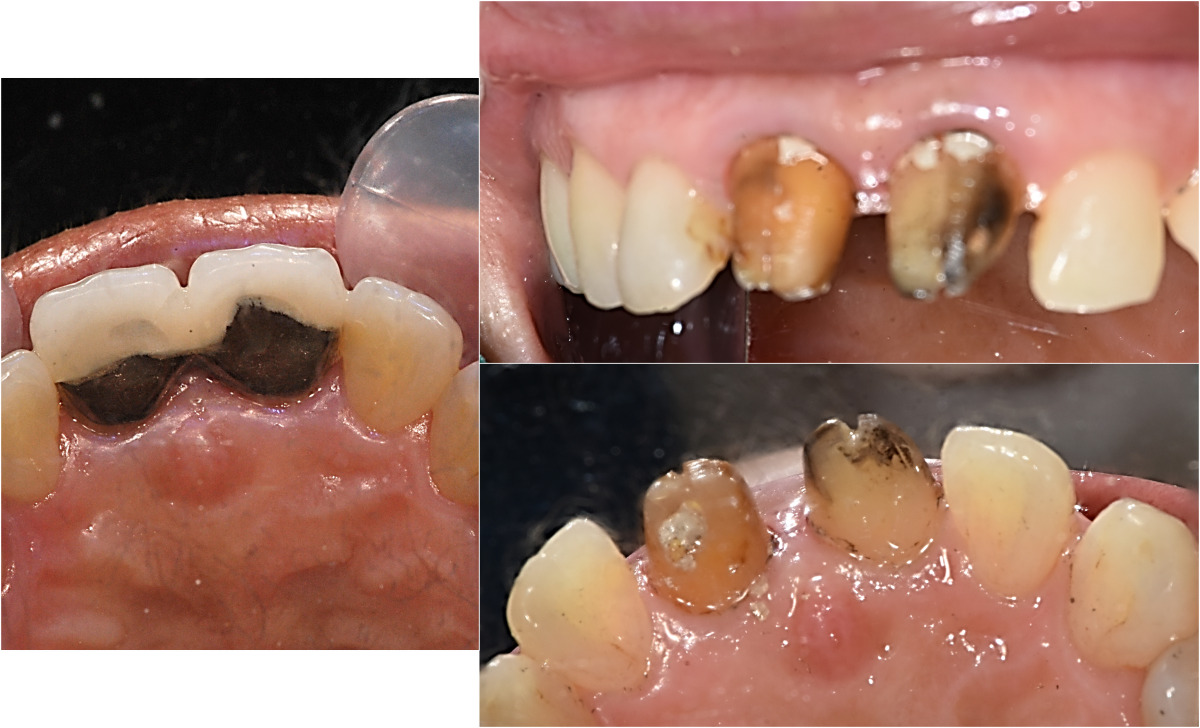

Apicorctomy /central incisor /GBR ; 6-year follow up.

<CJ SBN> Apicorctomy /central incisor /GBR ; 6-year follow up.